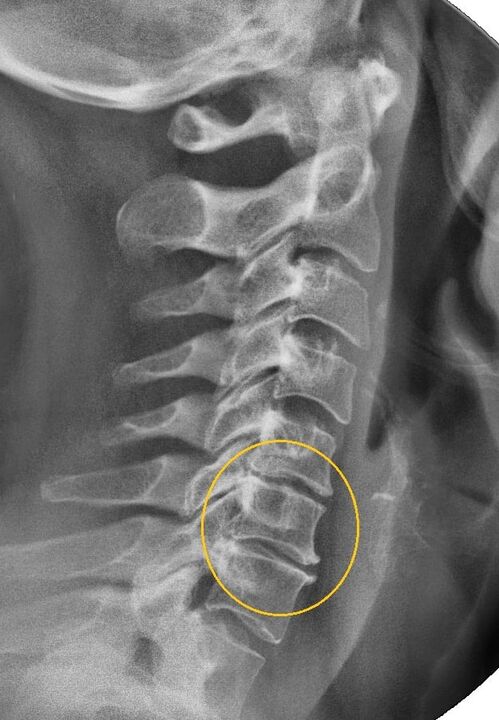

Najinformativnija dijagnostička metoda je radiografija. Patologije 1. stupnja odgovaraju 1. ili 2. radiološkom stadiju. Dobivene slike vizualiziraju tipične znakove bolesti.

| X-ray faze cervikalne osteohondroze 1. stupnja | Karakteristični znakovi |

|---|---|

| 1. faza | Manje promjene u zakrivljenosti kralježnice u cervikalnom području, koje zahvaćaju jedan ili više segmenata |

| Faza 2 | Lagano zadebljanje intervertebralnih diskova, deformacija uncinatnih nastavaka, ispravljanje lordoze, manje izrasline koštanih struktura. |